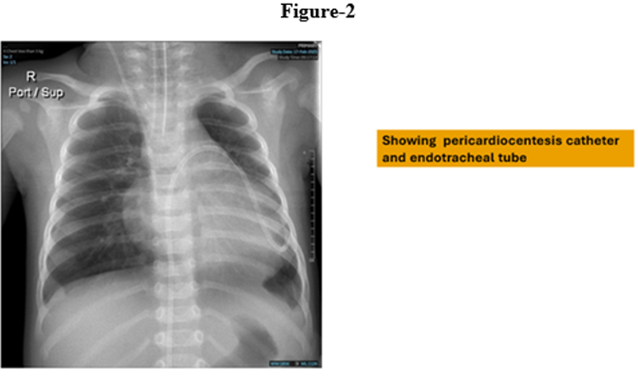

We report a four-month-old girl who presented in sudden cardiorespiratory collapse to illustrate an uncommon cardiac first sign of MTO1-related disease. The infant arrived hypotensive and obtunded with severe metabolic acidosis (pH 6.59; lactate 29 mmol/L). Chest radiograph showed cardiomegaly and bedside echocardiography revealed a large circumferential pericardial effusion producing compression of the right heart together with concentric left-ventricular hypertrophy. Emergency pericardiocentesis drained 120 mL of serous fluid and produced only transient improvement; over a prolonged PICU stay she had recurrent sterile effusions, four failed extubation attempts, refractory lactic acidosis, renal dysfunction and progressive bradycardia. Whole-exome sequencing identified a homozygous pathogenic MTO1 variant (NM_012123.4:c.1232C>T; p. Thr411Ile); both parents were heterozygous carriers. The family history included consanguinity and a sibling who died in early infancy after a similar illness. Despite maximal supportive care, she died on day 40 from cardiogenic shock and multiorgan failure. The case highlights that recurrent sterile pericardial effusion in an infant with hypertrophy and marked hyperlactatemia should prompt consideration of an underlying mitochondrial (MTO1-related) disorder and early genetic testing to guide counselling

Emergency pericardiocentesis was performed on her with drainage of 120 ml serous fluid. High-dose care included mechanical ventilation, inotropes, repeated bicarbonate infusion and metabolic coenzymatic focus (CoQ10, thiamine, biotin, folinic acid, L-carnitine) [5,6]. Riboflavin and dichloroacetate were also considered but not available [7]. The course was complicated with repeated pericardial effusions, four unsuccessful extubation trials, persistent lactic acidosis, renal failure, and progressive bradycardia. The patient had recurrent tamponade, despite multiple pericardiocenteses. Following multidisciplinary discussion of the dire prognosis and lack of disease-modifying therapy, a DNR was accepted by family. Day 40 she succumbed to cardiogenic shock.